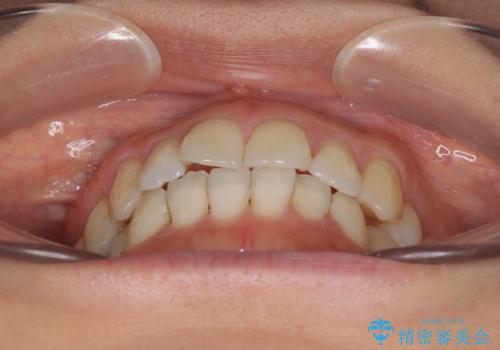

- 上下奥歯の欠損を気にして来院された患者様です。

以前矯正した後戻りにより前歯に叢生が認められたため、矯正治療の提案をしたところ、補綴治療と合わせて矯正治療を行うこととしました。

下顎欠損部はインプラントにて、上顎中間欠損部はブリッジによる補綴治療を行い、他にも気になっている銀歯をセラミックインレーやゴールドインレーにて修復治療を行うこととしました。

後戻りの程度は軽度であったため、インビザライン・ライトを用いて歯列を整えました。

再度後戻りするリスクを最小限に食い止めるため、下顎前歯の舌側を細いワイヤーで固定しました。